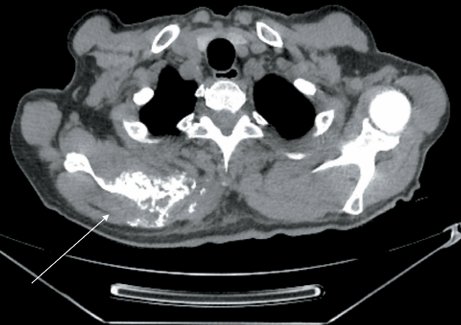

2. Рис. 2. МСКТ органов грудной полости (18.10.22): образование правой лопатки после 4 циклов комбинированной терапии по схеме: атезолизумаб + бевацизумаб + карбоплатин + + паклитаксел. В ости и верхней трети правой лопатки визуализируется объемное мягкотканое образование, размерами 80×57×73 мм (ранее 68×104×68 мм). Примечание: рисунок выполнен авторами